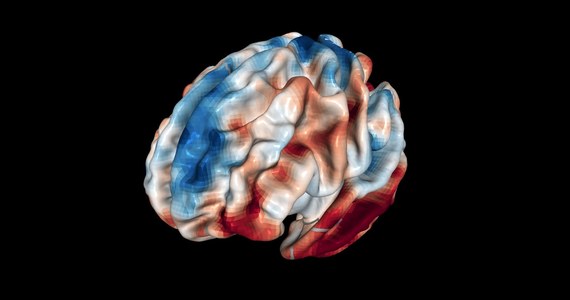

Naukowcy z Triestu wiedzą już, gdzie w naszym mózgu zapada decyzja, by komuś wybaczyć. Na łamach czasopisma "Scientific Reports" opisują wyniki badań wskazujących też, że nasza zdolność do puszczenia czyjejś winy w niepamięć ma swoje anatomiczne uwarunkowania. Jak się okazuje, w przypadku win nieumyślnych, chętniej wybaczają osoby, których przednia bruzda skroniowa górna (aSTS) zawiera więcej szarej materii.

Badacze SISSA (Scuola Internazionale Superiore di Studi Avanzati) wskazują, że skłonność do wybaczenia w przypadkach, kiedy ktoś popełnił wobec nas winę nieumyślnie, bądź nieświadomie, wiąże się z naszą umiejętnością oceny nie tylko wagi przewinienia, ale też intencji osoby, która je popełniła. Ta ocena dokonuje się właśnie w obszarze aSTS; im jest on większy, tym bardziej nam w tym pomaga.

Z przypadkami nieumyślnej winy mamy do czynienia często - może to być nie dość skoncentrowany kierowca, który doprowadza do wypadku, czy rozkojarzony współpracownik, który popełnia poważny błąd. Badacze z SISSA w Trieście postanowili sprawdzić, jakie rejony mózgu uczestniczą w procesie, który sprawia, że nad poważnymi, ale przypadkowymi winami jesteśmy w stanie przejść do porządku dziennego. Szczególnie interesowali się rejonem przedniej bruzdy skroniowej górnej.

Wcześniejsze badania pokazały już, że jeśli intencje działania i jego wynik stoją w jaskrawej sprzeczności, jak to bywa w przypadku nieumyślnych przewinień, przy formułowaniu ocen koncentrujemy się właśnie na intencjach - mówi główny autor pracy Indrajeet Patil. Do tej pory nie było jednak wielu prac, podchodzących do sprawy od strony anatomicznej. Nasze badania zmierzały do wyjaśnienia, czy różnice objętości i struktury pewnych rejonów mózgu mogą mieć wpływ na nasz osąd moralny - dodaje.

Badacze, pod kierunkiem Giorgii Silani, poprosili o udział w eksperymencie 50 osób. Ich zadaniem była ocena bohaterów 36 historii, przebiegających zgodnie z 4 scenariuszami. Były tam sytuacje, w których świadome działanie prowadziło do negatywnych lub neutralnych skutków, a także takie, w których do negatywnych lub neutralnych skutków prowadziły zdarzenia przypadkowe, niezależne. W każdym przypadku badani mieli ocenić uczestników danej historii w skali od 1 do 7 i odpowiedzieć na pytania o poziom ich odpowiedzialności i to, czy ich zachowania były moralnie dopuszczalne. Podczas testów mózg uczestników był poddany badaniom aktywności za pomocą aparatury rezonansu magnetycznego.

Odkryliśmy, że indywidualne oceny moralne uczestników mają związek z objętością materii szarej w obszarze ich przedniej bruzdy skroniowej górnej. Im wiekszy aSTS, tym większa ich pobłażliwość, nawet wobec osób, które spowodowały konkretne szkody - mówi pochodzący z Indii Indrajeet Patil. Wiemy już od pewnego czasu, że aSTS ma udział w ocenie myśli, przekonań, czy pragnień innych. Teraz widać, że jeśli jest lepiej rozwinięta, ułatwia nam dostrzeżenie przypadkowej natury przewinienia. Przy ocenie moralnej na tym właśnie się koncentrujemy, i w naszej ocenie ma to istotniejsze znaczenie, niż nawet nieprzyjemne skutki czyichś działań. To sprawia, że mamy mniejszą skłonność, by kogoś potępić - podkreśla.